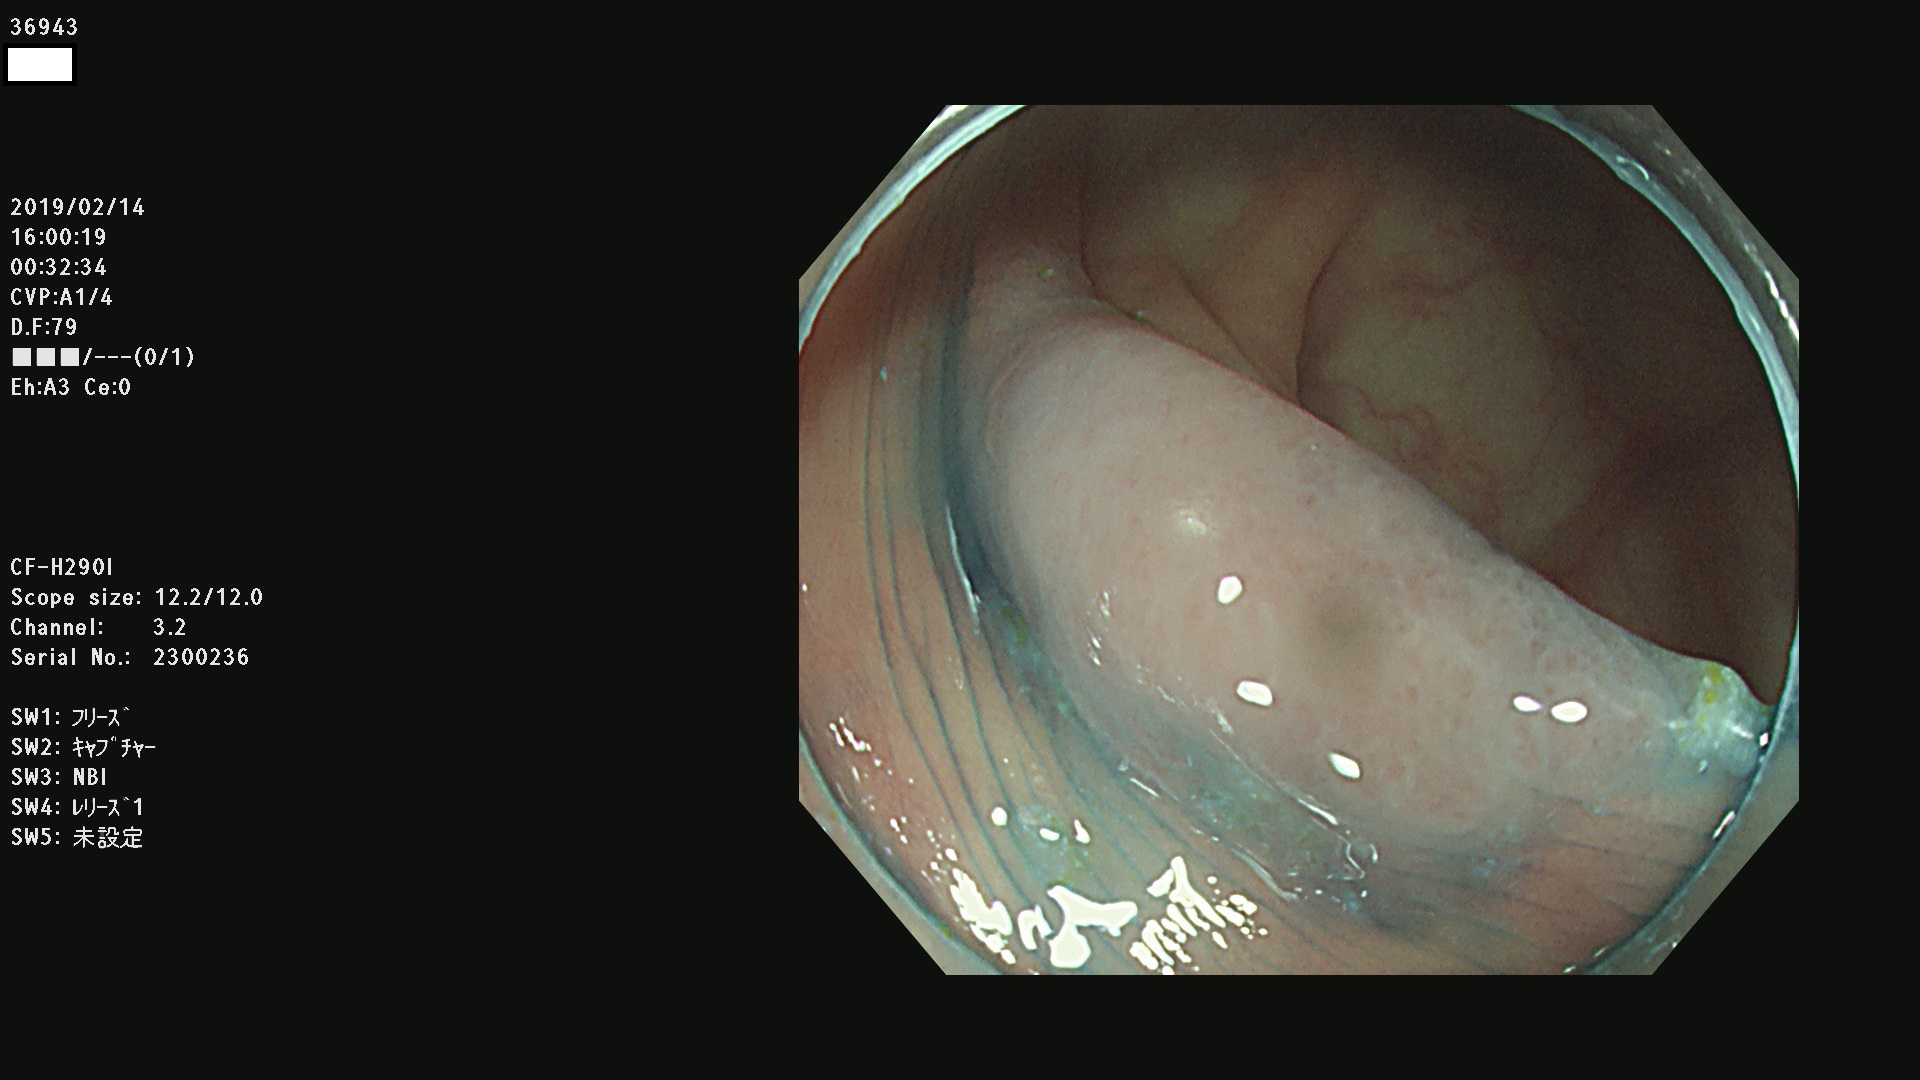

発見困難で危険性の高い平坦型病変(上記100名より抽出) ![]()